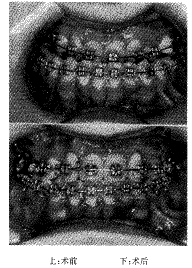

12例不同类型的上下颌骨牵引成骨患者,其牵引成骨的方向和牵引长度除1例外均达到术前设计要求,全部病例的成骨质量均满意,无感染,无成骨不良和牵引方向失误等并发症发生(图6~8)。

图6 手术前后正面像

图8 手术前后

像